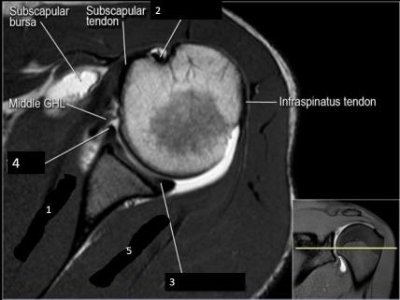

1. Observe a imagem acima. Que estrutura está rotulada com o número 2?